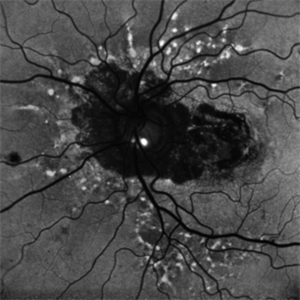

FAF showing angiod streaks , optic disc drusen, and macular atrophy secondary to macular neovascular membrane.

Condition/keywords: Angioid Streaks, macular atrophy, optic disc drusen